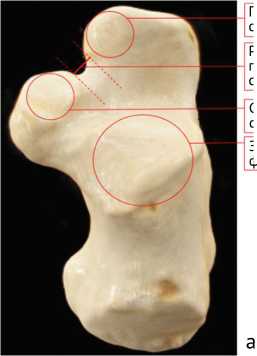

Всем пациентам выполняли мультиспиральную компьютерную томографию (МСКТ) стопы. Полученные изображения последовательно обрабатывали, в результате получали 3D-модель пяточной кости с визуализированными на ней суставными фасетками. Оценивали их форму и расположение.

Систематизацию расположения суставных фасеток подтаранного сустава проводили по классификации P. Bunning и C. Barnett [14]:

• —    тип A: пяточная кость имеет три отдельно расположенные суставные фасетки;

• —    тип B: пяточная кость имеет объединенную переднюю и среднюю фасетки и отдельно расположенную заднюю;

• —    тип C: пяточная кость имеет одну суставную фасетку, объединяющую переднюю, среднюю и заднюю.

Для осуществления лечения пациентов предлагаемым методом на предоперационном этапе проводили МСКТ стопы пациента, создавали 3D-модели пяточной кости, на поверхности которой визуализируются суставные фасетки, определяли их расположения и формы по классификации P. Bunning и C. Burnett, после чего выполняли ряд измерений. Проводили предполагаемую линию остеотомии между суставными фасетками (между передней и средней, если остеотомия выполняется по Evans; между средней и задней, если остеотомия проводится по Hintermann). От пяточно-кубовидного сустава опускали перпендикуляр к линии остеотомии и определяли угол ее наклона относительно латеральной стенки пяточной кости (рис. 2).

Расстояние между передней и средней суставными фасетками

Передняя суставная фасетка

Средняя суставная фасетка

Задняя суставная фасетка

Расстояние между передней и задней суставными фасетками

Объединенная передняя суставная фасетка

Рис. 2. Расположение суставных фасеток подтаранного сустава на 3D-модели пяточной кости (а) и методика определения угла наклона остеотомии относительно наружной стенки пяточной кости (б)